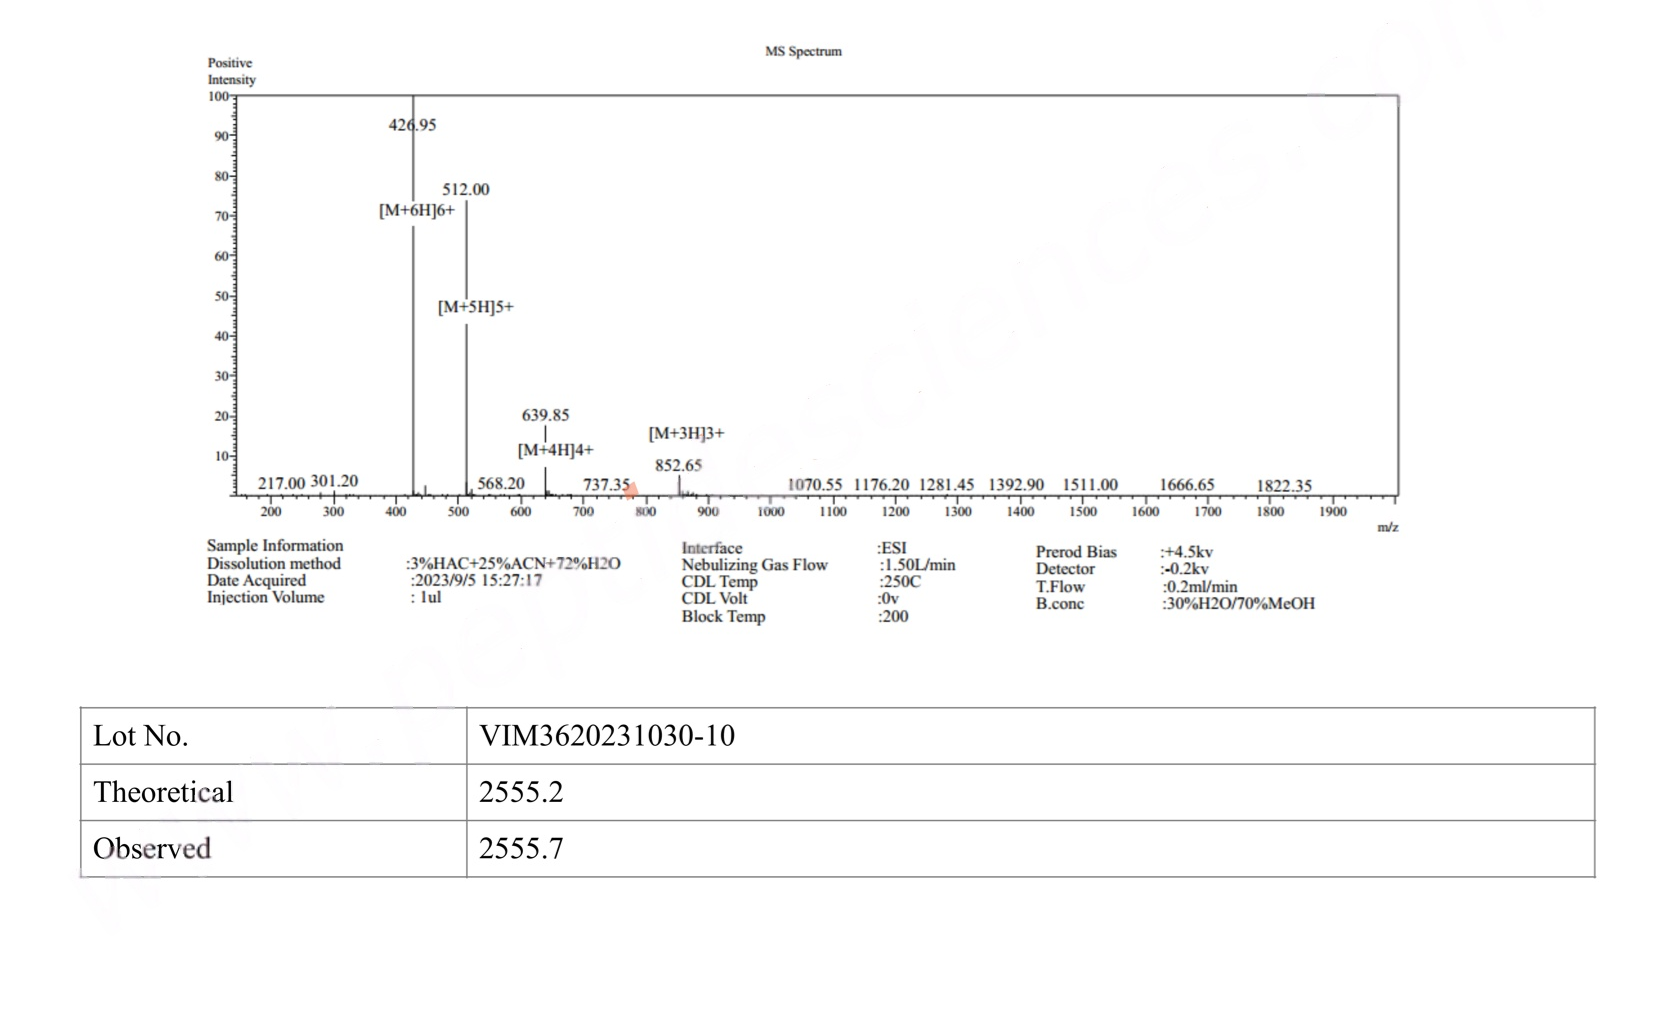

MS Adipotide (FTPP) Certificate